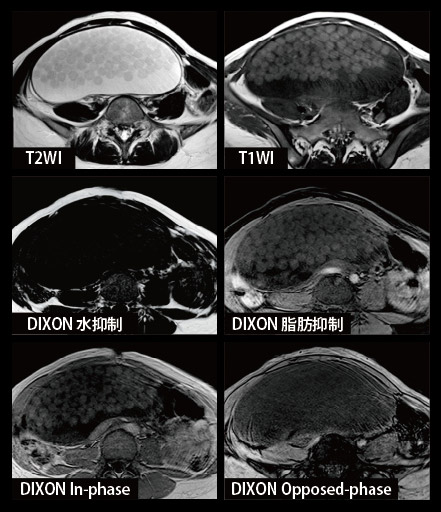

Mri t1 t2 腹部. Mriはctと違いx線を使わないため放射線被ばくになることはありません。 mri画像の色の違いとは? mriもct同様に白と黒で画像表示されます。 mriでよく使うのがt1画像とt2画像です。 t1とt2の見え方については表をご覧ください。 t1画像. 現在、当クリニックでは上腹部MRI検査として、横断像を4シーケンス<T1(in、 out Phase)T2 HeavyT2 DWI>、冠状断を1シーケンス<HeavyT2>を撮影ルーチンとしております。スライス厚は5mmを基本として35枚程度の撮影です。. Open MRIの高い性能を感じ取ることができる。 (1) 基本的シーケンス Open MRIでは、MRI検査に必要な基本シーケンスを撮像 することができる。具体的にはT1強調画像、T2強調画像、プ ロトン密度強調画像、T2*強調画像、MRAngiographyなど である。.

MixiMRI勉強会 脂肪抑制いろいろ 最近やっと勉強する気になったのですが、疑問が次から次へと出てきます。ここでは脂肪抑制についてお聞きしたいと思います。 脂肪抑制にもいろいろありますよね。 T2、PD、T1など。また、SE系、GRE系の違いもありま. ・骨盤部ではmriを,腹部ではctを第一選択にする. ・t1強調画像ではt1が長いほど磁化の回復が遅れるため信号が低く(黒く),t2強調画像ではt2 が長いほど磁化の減衰が遅れるため信号が高く(白く)描出される.t1とt2の組み合わせで組 t1強調画像はctの画像と似ており、脳の解剖学的な構造が見やすいという特徴があります。. 造影剤投与によりT1緩和時間が大きく短縮されますので基本的に脂肪抑制T1強調画像をベースに撮影が行われます。 ③実際の症例を提示します。 1) Stage I 腎細胞癌のdynamic MRI画像です。 左腎臓上極に1cm大の遷延性濃染する腫瘍を認めます。.

MRIは、磁気共鳴画像(Magnetic Resonance Imaging)の略称で、 強い磁石 と 電波 を使って体の断層像を撮る検査です。 MRIの原理は、まず強い磁気の中で、患者さんに外から電波を体に加えます。. ・骨盤部ではmriを,腹部ではctを第一選択にする. ・t1強調画像ではt1が長いほど磁化の回復が遅れるため信号が低く(黒く),t2強調画像ではt2 が長いほど磁化の減衰が遅れるため信号が高く(白く)描出される.t1とt2の組み合わせで組織 の成分が推定できる.. Mri造影剤は、mriにおける体内構造の可視性を向上するために使われる造影剤 。 コントラストの強調にはガドリニウムという化合物が最も一般的に使われる。 このmri造影剤は経口投与もしくは静脈投与(angio)により体組織内の核の緩和時間を短縮する。.

MRI(magnetic resonance imaging)検査では撮像 時間が長く,上腹部の検査では,呼吸による動きによ ってモーションアーチファクト(mortion artifact:運 動アーチファクト)が発生し,読影診断に影響を与え てしまうおそれがある.呼吸のような周期的な動きに. 3T MRI が臨床に導入されてから、基本的な撮像技術の重要性がますます高まっている。本講演では、3T MRIにおける躯幹部領域のトピックスである、脂肪抑制、Volume化の流れ、非造影MRAの3点について、GE社MRIの最新アプリケーションと臨床的有用性を中心に紹介する。. く,造影剤が分布した周囲組織のプロトンの緩和を促進(主としてt1短縮効 果)させることにより,t1強調画像で造影効果を発揮する(信号が増強される)。 しかしながら,造影剤濃度が高くなると,t2,t2*短縮効果により信号は逆に 減衰する(図1)2)。.

〈medix vol.50〉 41 1.はじめに mri検査において基本シーケンスはt2強調画像とt1強調 画像である。かかりつけ医の医療の場において、診断能向上の. 頭部MRI の基礎 -頭部MRI で撮られる各画像について- 友愛会南部病院 仁井田 明 要旨 現在、日常的に撮影されている頭部MRI(Magnetic resonance imaging :磁気 共鳴画像法)画像にはT1 強調像(T1WI)、T2 強調像(T2WI)、プロトン密度強 調像(PDWI)あるいはFLAIR(FLuid-Attenuated Inversion Recovery)像. 3T MRIの組織コントラスト能の特徴 T1強調画像 de Bazelaireらの研究 1) によると,腹部領域における3Tと1.5Tの緩和時間の違いは,肝臓,脾臓,膵臓では,3TでT1値が著明に延長するのに対し,筋肉では緩和時間に差がなく,結果的に,3Tでは肝臓,膵臓,筋肉でのT1値の差が少なくなる。.

上腹部mriの見方 シーケンスを4つに分類しよう 画像診断 Com